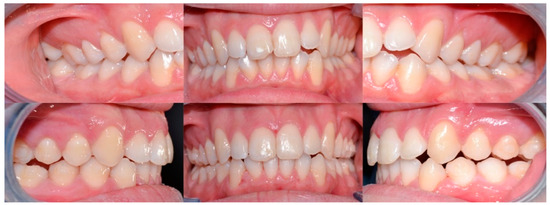

2.3.2. Example 2—Extraction Space Closure